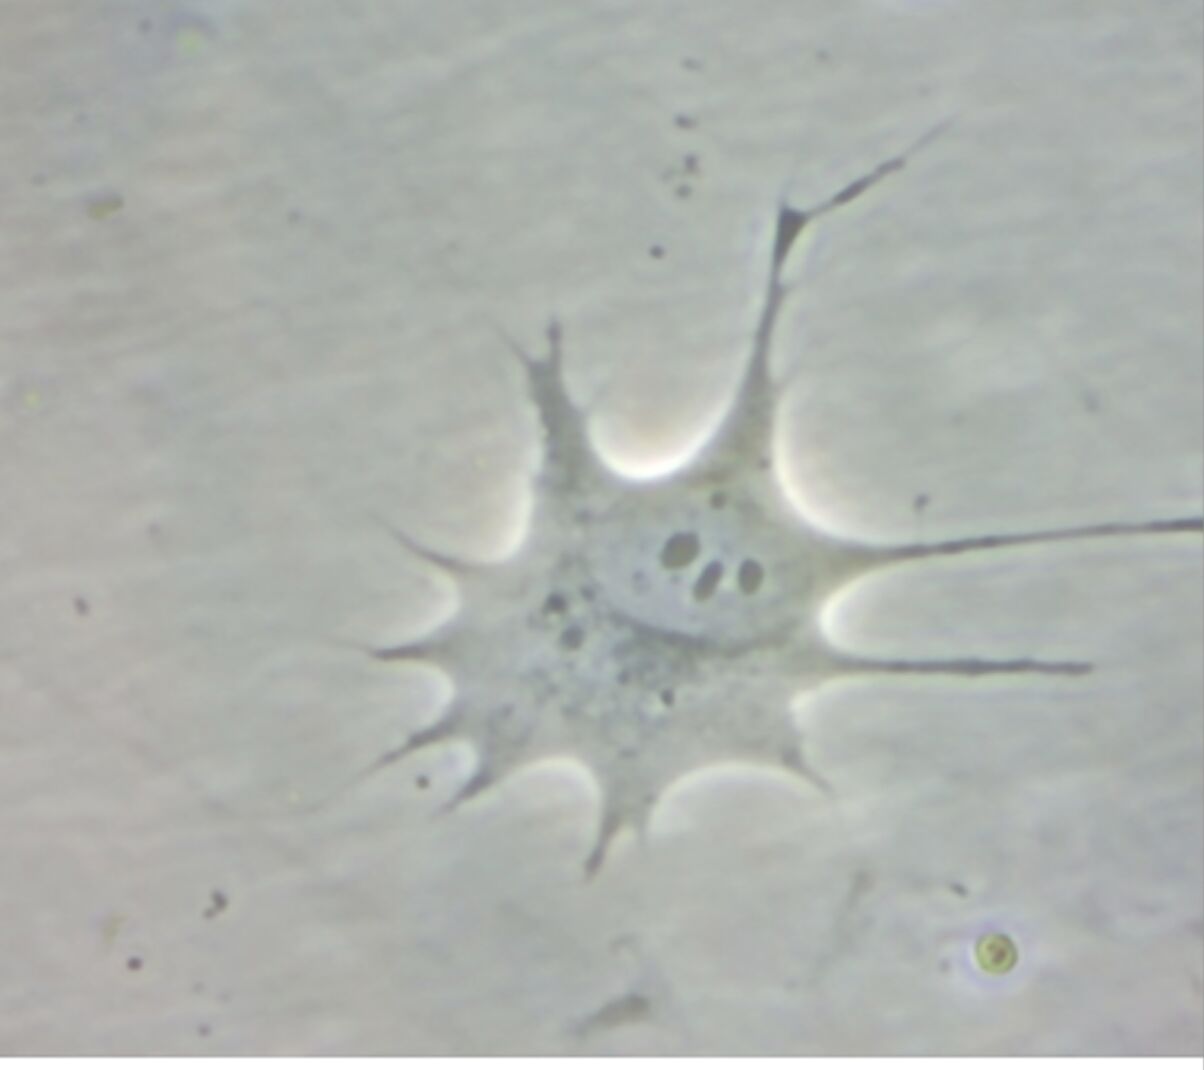

As you can see in the image shot by Wilhelm, cells are in a great mood and look forward to being used.